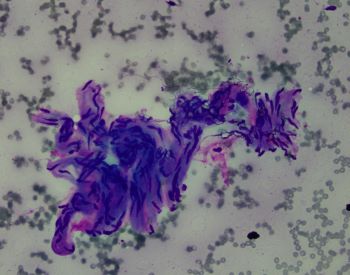

A fine needle aspiration of pancreatic head lesion/mass was performed and the specimen consists of loosely arranged small groups of spindle cells with scant cytoplasm and oval elongated and regular nuclei. Nucleoli are not seen. Ganglion cells are also present (two present in the lower half of the IHC image of the question).